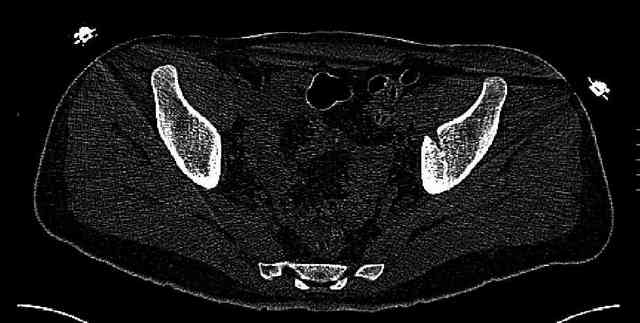

Re: Нелеченный перелом вертлужной впадины

Some more images. Does it help to guess which part of the acetabulum is displaced?